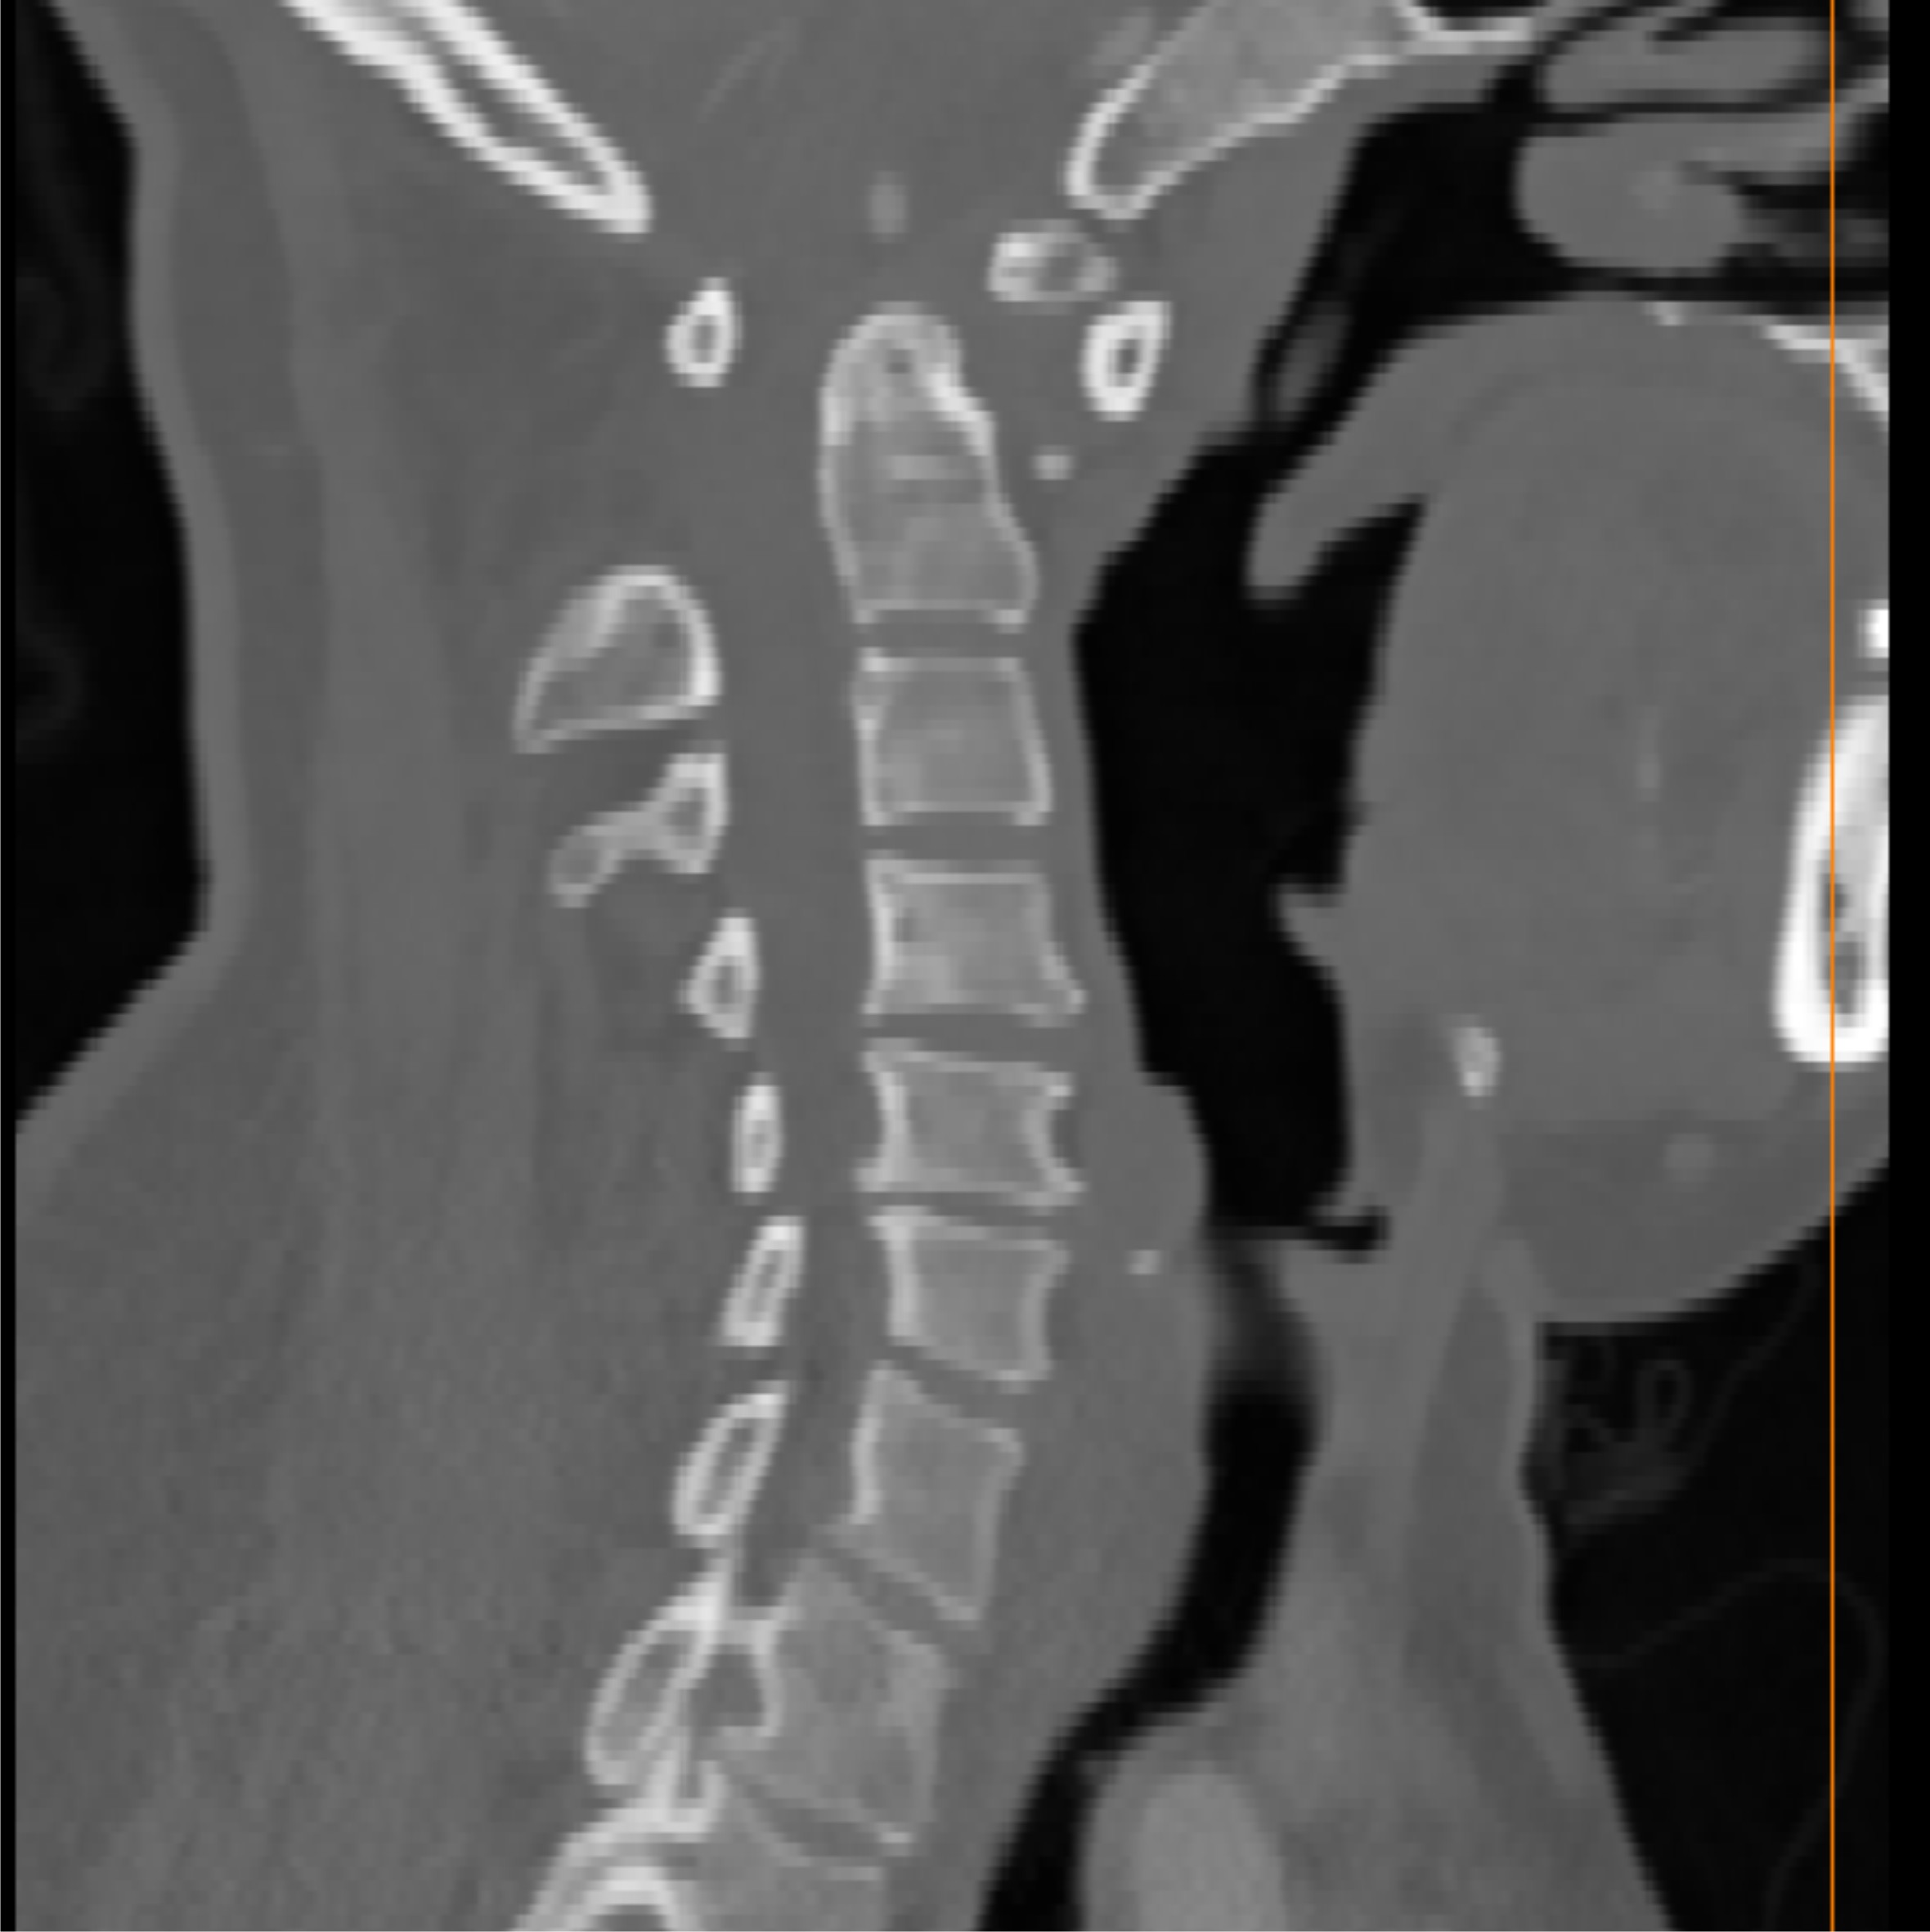

定制化导航板设计

精准定位、导向

术前规划

采集患者CT/MRI数据